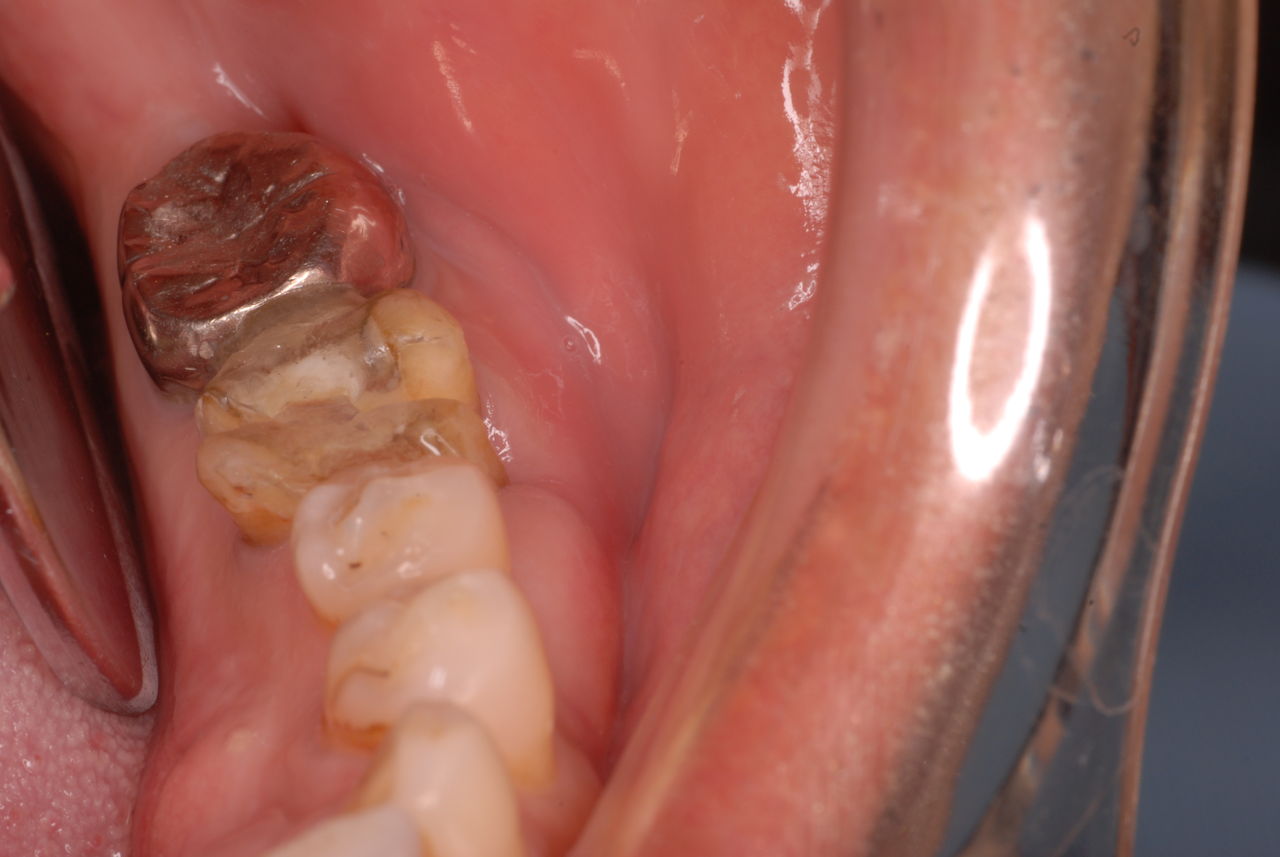

他の都心の矯正歯科で治療中で、ほぼ終了近くの方でした。歯並びで言えば上下の歯が突出していて唇が閉じにくいというのをなんとかしたい。そして歯を抜かないで出来るところを探して都心の矯正歯科への通院となりました。ところが本人曰くよく噛めないというのです。

相談しても“問題無い”の説明だけだそうです。調べたところ歯周病は進行しているし、奥歯の大きい歯2本ずつ計4本はしっかり噛んでいないのです。よく噛めないというのはそのことのようでした。これを矯正的に元に戻すことはできない訳ではありませんが、時間と手間がかかるのは間違いないことです。